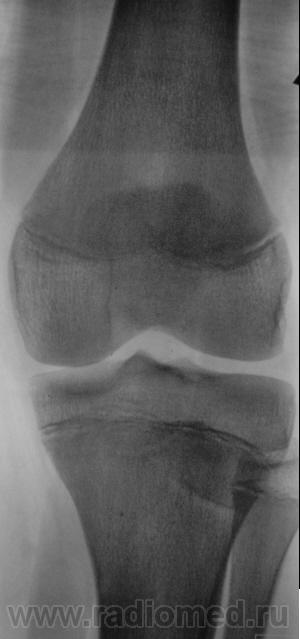

Пациент направлен на рентгенографию коленного сустава с диагнозом - Болезнь Осгут - Шлаттера.

фрагментация бугристости Б\Б кости

Трактовать надо так: до 18 лет это-остеохондопотия; после 18лет это асептический некроз.

А может "норма"? А может вариант развития бугристости?

Болезнь Осгут - Шлаттера, как-то не вдохновляет. Более склонен к консоидирующемуся отрывному перелому бугристости б/берцовой кости.

Более склонен к варианту окостенения, хотя травматический генез, как и асептический некроз (абсолютно согласен с Максималистом - при наличии клиники и анамнеза) с повестки дня окончательно, до выяснения оных, не снимаются.

Уважаемые коллеги! На мой взгляд, выявленное на рентгенограмме, образование костной плотности, с четкими, ровными контурами, однородное по своей структуре отношения с бугристости большеберцовой кости не имеет. Хотелось бы знать возраст пациента, его анамнез (спорт, травмы области коленного сустава). Больше похоже на обызвествления собственной связки надколенника. Дополнил бы УЗИ коленного сустава.